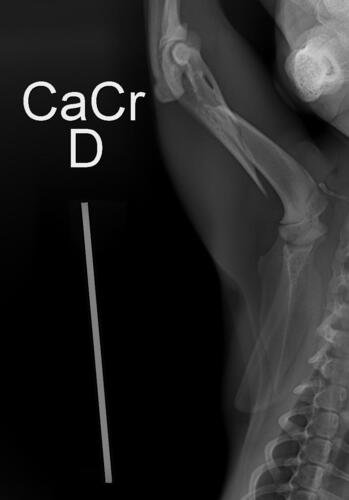

Meu gatinho sofreu um acidente,onde fraturou o osso da pata direita e necessita de cirurgia.No momento eu não tenho condições de pagar a cirurgia porque sou assalariada e o toda a reserva de dinheiro já foi com medicações e exames.